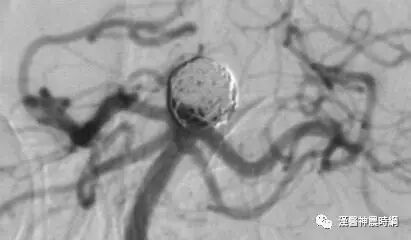

颅内动脉瘤是指脑动脉内腔的局限性异常扩大造成动脉壁的一种瘤状突出,颅内动脉瘤多因脑动脉管壁局部的先天性缺陷和腔内压力增高的基础上引起囊性膨出,是造成蛛网膜下腔出血的首位病因。过去人们称之为先天性脑动脉瘤,事实上先天性脑动脉瘤占脑动脉瘤的70%~80%。

如果动脉壁呈不对称性囊状扩张,即称之为囊状动脉瘤,小的囊状动脉瘤有瘤颈狭窄者又称之为浆果状动脉瘤,绝大多数先天性动脉瘤呈囊状或浆果状,亦可呈小结节状,称之为分叶状动脉瘤,其他形态有葫芦状,圆球状,腊肠状等,瘤壁一般光滑如囊,多数由先天薄弱的血管壁构成,常位于较大动脉的分叉处,动脉瘤与载瘤动脉相连处较狭窄,称为瘤颈(蒂)或基底,瘤颈宽窄很不一致;与瘤颈相对的远侧最突出的部分为瘤底(顶),介于瘤颈与瘤底之间的部位称为瘤体(囊),小阜为瘤囊上小的隆起,常为动脉瘤发生破裂之处或破裂后的遗迹。

先天性动脉瘤的大小悬殊很大,通常在0.5~2cm,小的须用放大镜才能看到,未破裂前不产生临床症状,可在尸检中发现,大的可达橘子大小,而产生明显的占位性表现,文献中报道动脉瘤直径可达8cm以上,最大者直径为12cm,绝大多数能产生症状的动脉瘤直径在0.7~1.0cm,直径小于0.3cm者很少产生症状,多偶然发现,动脉瘤的破裂与其大小有一定关系,小于0.3cm的动脉瘤破裂机会较少,一般认为破裂的动脉瘤较大,未破裂的动脉瘤较小,动脉瘤破裂的临界大小为直径在0.5~0.6cm,直径超过0.5cm的动脉瘤出血机会逐渐增多,其直径超过3.0cm后,则颅内压增高的症状取代了出血症状,并非动脉瘤越大,破裂出血的机会越多,这是因为巨大型动脉瘤腔内常有多量分层的血凝块,加固了瘤壁,因此,破裂出血的机会相应地减小,大的动脉瘤可见于任何年龄,年龄愈大,大的动脉瘤发生率也愈高,约50%以上的巨大型动脉瘤病人年龄在45岁以上。